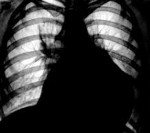

На рентгенограмме при значительном объеме жидкости наблюдается увеличение тени и сглаживание сердечного контура, изменение формы сердца (треугольная - при длительно существующем хроническом экссудате), ослабление пульсации сердца.